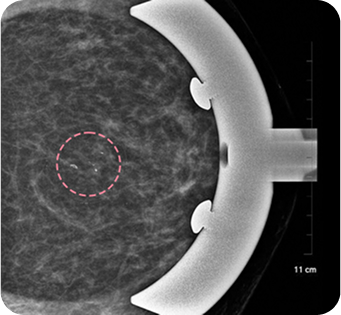

양성 종양은 여러 개가 동시에 생겨나기도 합니다. 정상적인 유방 조직 보전에 신경 쓰며 맘모톰 시술을 섬세히 진행했고, 6개월 뒤 추적 관찰을 위한 유방초음파에서 종양이 깨끗이 제거된 것을 확인 했습니다. 일부 반흔 조직은 자연스럽게 호전될 것으로 보여 좋은 예후가 기대되었습니다.